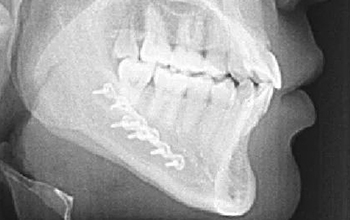

At CZMEDITECH, we are dedicated to providing reliable orthopedic solutions through real clinical success. Each surgical case reflects our continuous innovation in spinal fixation, trauma management, joint reconstruction, maxillofacial repair, and veterinary orthopedics. By integrating advanced manufacturing technology with the expertise of experienced surgeons, we ensure every implant delivers safety, precision, and long-term recovery.

Explore below a selection of clinical cases that demonstrate how our CE-certified implants help restore mobility, stability, and confidence in patients worldwide.